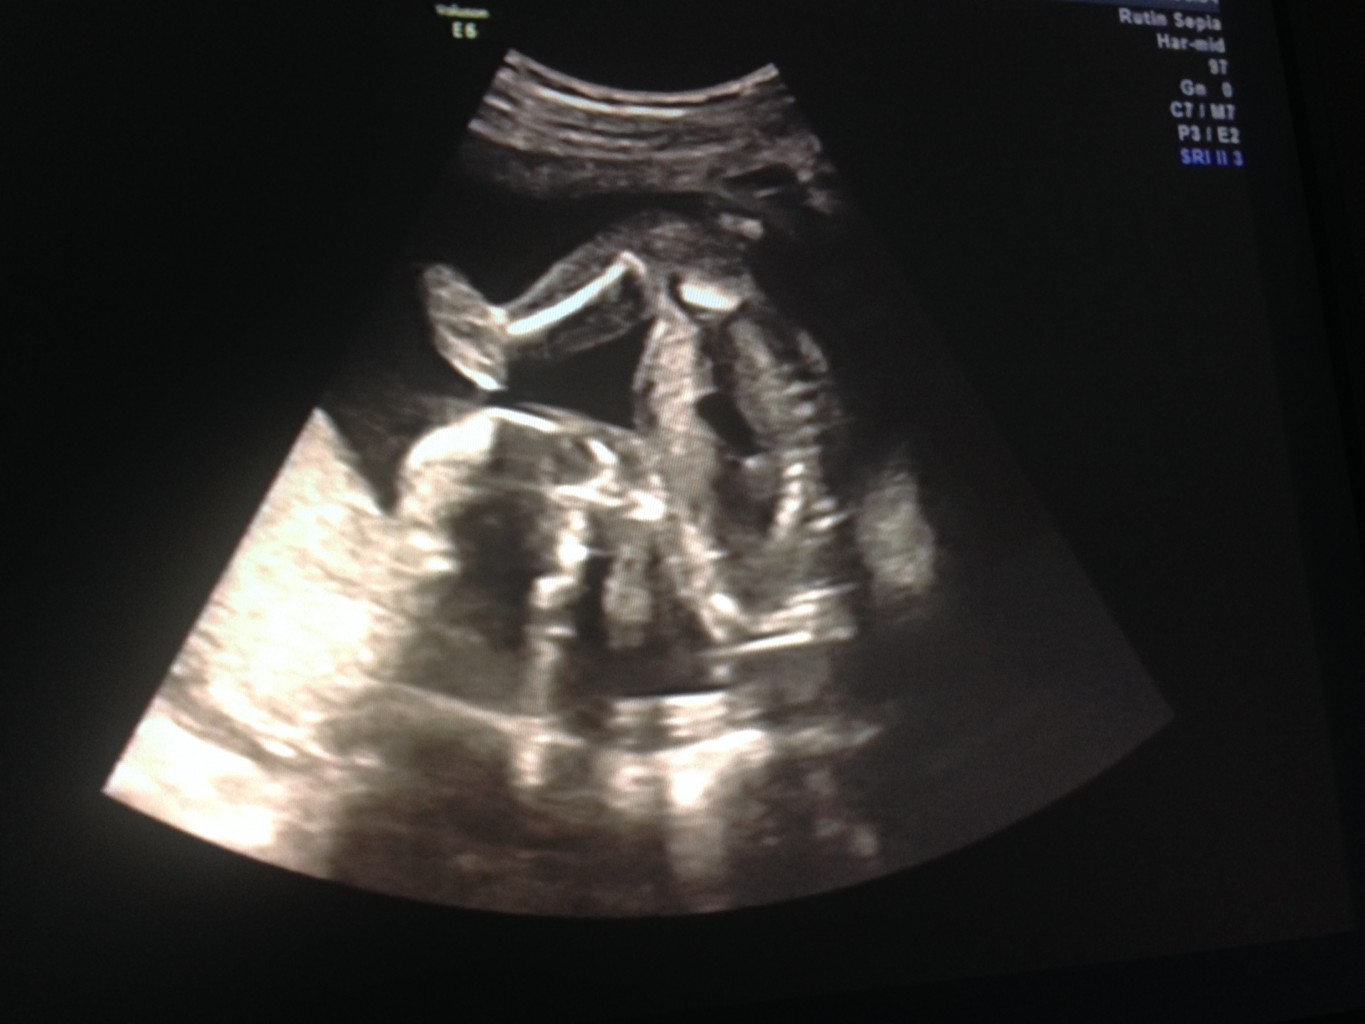

Senast jag var och gjorde ultraljud på östra sjukhus så glömde jag att lägga upp bild på vår älskling så här kommer den nu i efterhand.

Detta va det första riktiga ultraljud som vi gjorde där vi får veta om hjärtat är rätt och sitter rätt , slår rätt och det gjorde det, hjärnan utvecklades rätt och och huvudet var inte större än en liten golfboll. hehe så gulligt. Men gud vad han va aktiv och gjorde Valter i min mage , sjukt underbart och titta på. Kan fortfarande inte fatta att jag ska bli mamma eller att jag och min älskling ska bli föräldrar till denna underbara fina krabat! Det går verkligen inte att beskriva kärleken man känner för någon man inte har träffat men ha vart där sen dag 1 . Kommer att bli underbart.